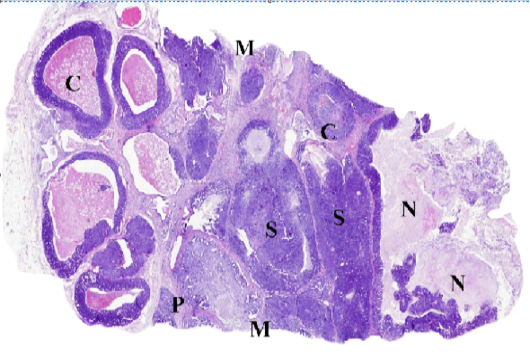

WSI of feline mammary gland tumor, resized, illustrating (C) Comedocarcinoma, (P) Tubulopapillary carcinoma, (S) Solid carcinoma, (N) necrosis and (M) surgical margins.